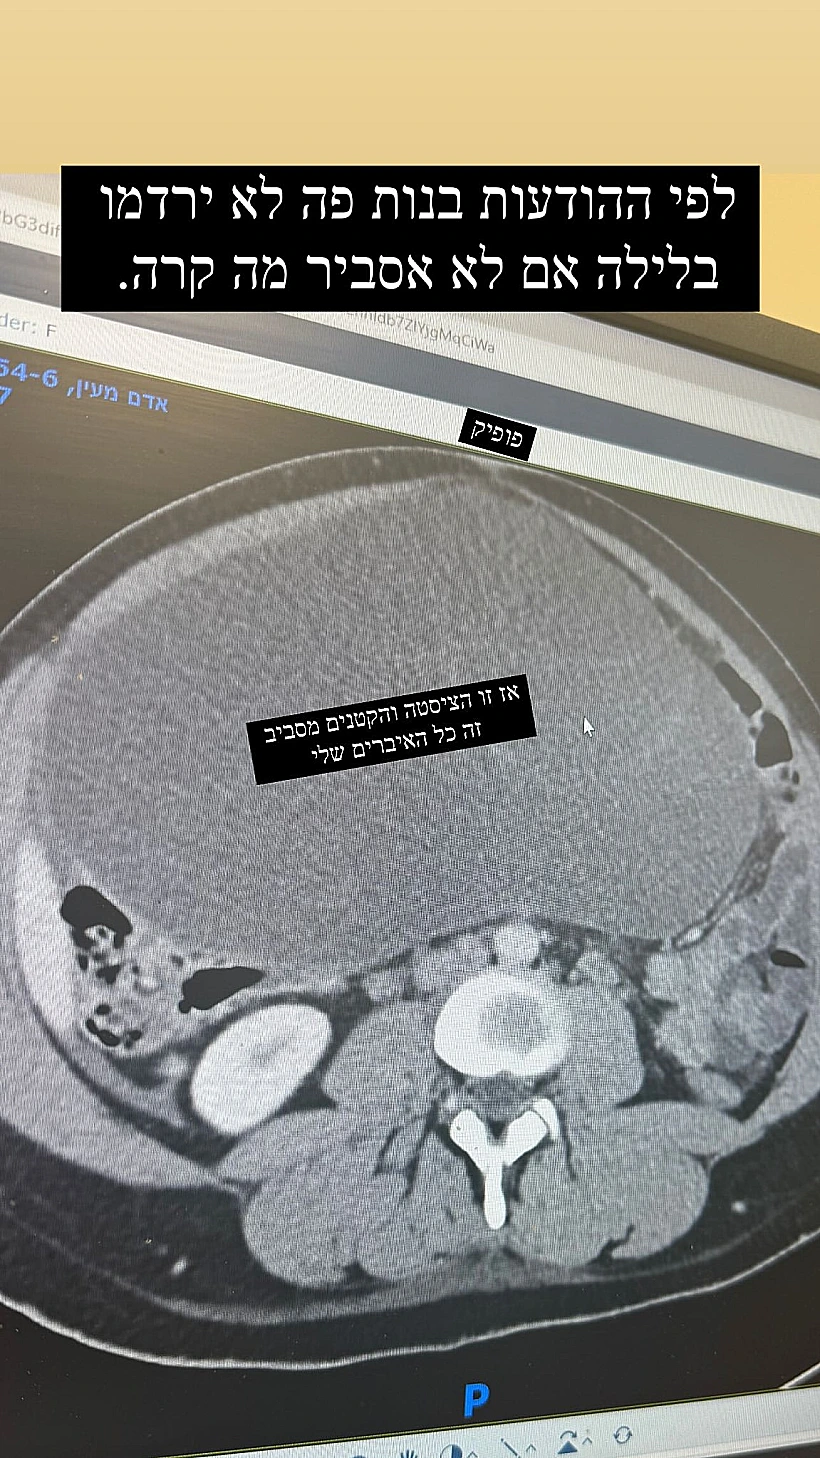

מלבד הלידה בשידור חי של אליקו ולירז ארז לא זכינו לשום עדכון בלתי פוסק על מצבים קריטיים של הכוכבים, הפעם נראה שמעיין אדם לא חוששת או נרתעת מלשלתף מאות אלפים במצב הרפואי שלה. מאז שיצאה מבית החולים לאחר לידת בתה השניה קדם, התלוצצה המגישה על הבטן שנשארה לה. בתחילת השבוע חשפה כי הובהלה למיון לאחר שנמצא גוש חריג בבטנה ושיתפה את העוקבים בכל צעד עד אתמול בערב, רגע הוצאתו. "יש לי ממצא בקוטר 25 סנטימטר בבטן, ציסטה כנראה, ענקית וחריגה. זה לא הרחם שכבר חזר לגודלו המקורי" סיפרה רגע לפני שנכנסה לחדר ניתוח. בסיומו של ההליך הרפואי שעברה, העלתה אדם תמונות שלה אחרי, וחשפה איך סיימה חמש קילו פחות.

אתמול לאחר שהספיקה להתאושש עדכנה את כל העוקבות שלה בסיפור המלא של מה שקרה: "אחרי הלידה ציסטה קטנה ושגרתית שהייתה על השחלה גדלה למימדים האלו. בצירוף מקרים חריג מבחינת טיימינג הרחם התכווץ אחרי הלידה והיא גדלה וכך בעצם לא שמתי לב לארוע החריג הזה כי הבטן נשארה פשוט באותו גודל, הם התחלפו אחד בשניה. הגעתי באמבולנס למיון בעקבות כאבים עזים ובאולטרסאונד ראו בלון ענק באמצע הבטן שלי והחלו בבדיקות. היה ברור שצריך ניתוח להוציא את זה אבל יש כל מני פרוצדורות שונות".

עוד הסבירה: "כיוון שלא יודעים מה יש בתוכה חייבים לנקז אותה כשהיא מחוץ לחלל הבטן (כי אם יש בה למשל תאים סרטניים שיתפזרו בבטן הלך עלי) וככה פערו בי חריץ קטן דרכו הוציאו מעט ממנה והחלו לשאוב את הנוזל. הצליחו לרוקן אותה ולהוציא אותה כמו בלון ריק דרך החריץ הקטן יחד עם השחלה שהיא צמחה עליה".